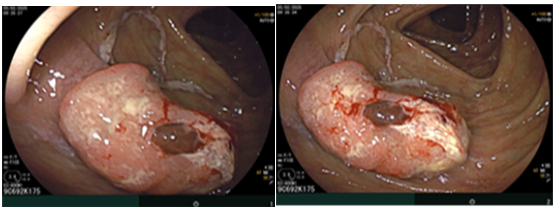

Sau đó bệnh nhân được nội soi dạ dày - đại tràng phát hiện đại tràng lên có khối lồi kích thước ~2.5cm, bề mặt nham nhở, cứng dễ chảy máu. Sinh thiết 03 mảnh. Giải phẫu bệnh: Ung thư biểu mô tuyến.

Hình 3. Tổn thương khối lồi xuất hiện ở vùng đại tràng lên

Nội soi đại tràng (thời điểm trước phẫu thuật T2/2025): Đại tràng lên có khối lồi kích thước ~2.5cm, bề mặt nham nhở, cứng dễ chảy máu.